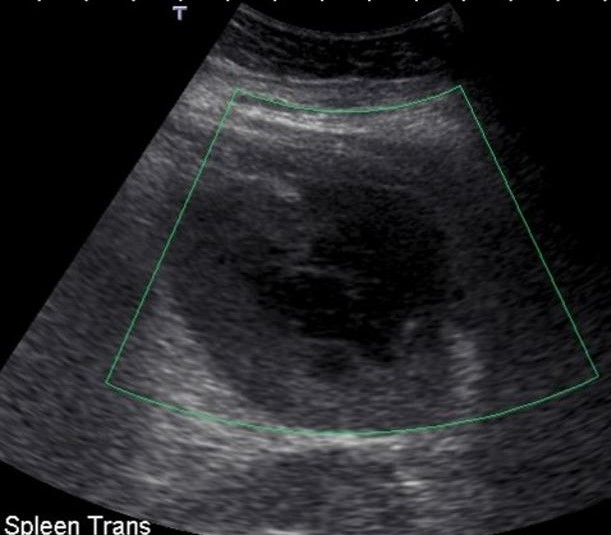

Картина острого холецистита может иметь разнообразные эхографические признаки, выраженность которых часто зависит от степени выраженности и особенностей течения заболевания у каждого конкретного пациента.

Суммируя общие признаки острого холецистита, можно отметить ряд наиболее частых и характерных особенностей ультразвуковой картины данной патологии. К ним относятся:

- увеличение размеров желчного пузыря

- изменения стенки желчного пузыря (изменения толщины, эхогенности, внутренней структуры и контуров стенки). Частым сонографическим признаком деструктивного процесса являются эхонегативные зоны в толще стенки желчного пузыря, наличие «двойного контура».

- изменения полости желчного пузыря (наличие разнообразных включений – конкременты, застойная и замазкообразная желчь, эхогенная взвесь, мелкие пузырьки газа и т.п.)

- изменения в перипузырных тканях (инфильтрация, отек, нарушения анатомических соотношений)

- выявление реакции лимфатической системы в виде локального лимфаденита

- признаки острого воспалительного процесса, выявляемые с помощью допплерографии

- осложнения течения острого холецистита (водянка, эмпиема, гангрена, эмфизематоз, перфорация, отслойка слизистой оболочки, перивезикальный абсцесс, холангит)

- динамичное изменение эхографической картины.

Рис.1 Утолщение стенки желчного пузыря, наличие «двойного контура»

Рис. 2 Утолщение стенки и наличие конкремента в просвете желчного пузыря

Ультразвуковое исследование (УЗИ) – приоритетный метод диагностики и мониторинга при остром холецистите. Всем больным в обязательном порядке на этапе приёмного отделения назначают УЗИ органов брюшной полости. Данный метод диагностики позволяет верифицировать диагноз и обозначить вектор лечебно-диагностического процесса при остром холецистите, ориентироваться в сроках операции и достоверно оценить течение пред- и послеоперационного периода.